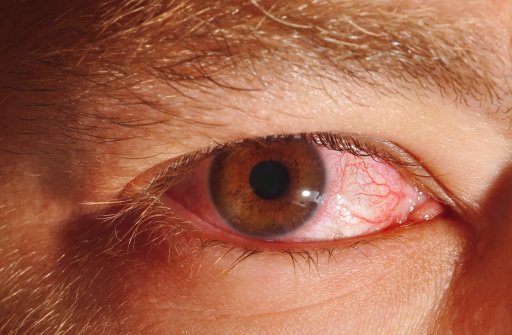

Chalazion eyelid cyst or Meibomian cyst (lump in eyelid): Causes, symptoms, and treatment

A chalazion is a lump inside the upper or lower eyelid, also known as a Meibomian cyst. The primary cause of a chalazion is inflammation of one of the small oil-producing glands located in the upper or lower eyelid. While it may get infected later on, a chalazion is not caused by bacteria, but is ...click here to read more